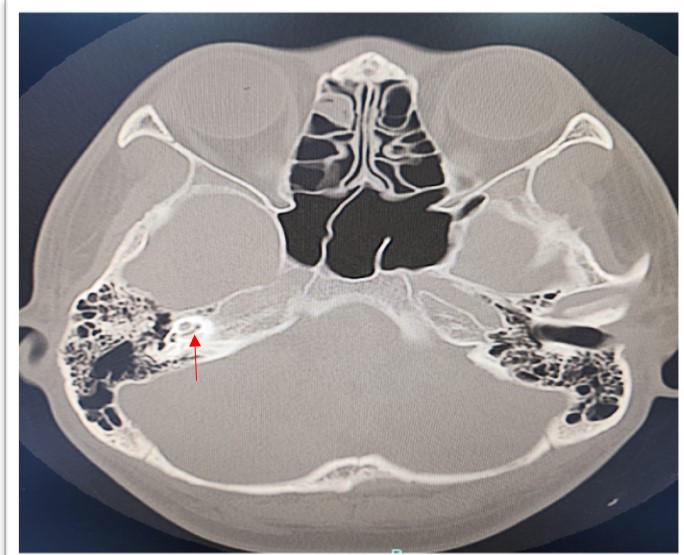

Coronavirus disease 2019 is a highly infectious disease. The complications of the disease markedly reduced after the introduction of vaccine. Thus, vaccination for COVID-19 is important and has been prompted in many countries. Reports on rare serious adverse events after COVID-19 vaccinations are well documented. The audio vestibular adverse event after COVID-19 vaccination have been reported. We herein discussed a case of labyrinthitis ossificans post COVID vaccination. A 23-year-old male presented with sudden onset right hearing loss (SNHL) with tinnitus 3 days after received COVID-19 vaccine. Pure Tone Audiometry (PTA) revealed right profound hearing loss with normal left hearing. High Resolution Computed Tomography (HRCT) of the temporal bone showed hyperdensity seen at the basal turn of the right cochlea, with Magnetic Resonance Imaging (MRI) revealed focal loss of normal T2-weighted hyperintense signal intensity of the scala tympani of the basal turn of the cochlear, suggestive of labyrinthitis ossificans. He was fitted with hearing aid and undergone for right cochlear implant for hearing rehabilitation. Labyrinthitis ossificans is commonly caused by infection and inflammation, and less commonly trauma, tumors, hemorrhage, or autoimmune inner ear disease. The correlation with vaccination is yet to be revealed and required further study.